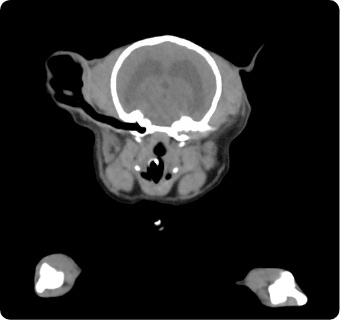

일산시티동물의료센터 영상의학센터는 최첨단 장비를 기반으로, 반려동물의 건강 상태를 보다 정확하고 신속하게

진단하는 핵심센터입니다. 고화질 CT와 초음파, 디지털 엑스레이, 투시촬영기기(C-arm)을 사용해

고해상도 영상과 정밀한 분석을 통해 질병의 조기 발견과 맞춤 치료 방향 제시를 목표로 합니다.

빠른 촬영속도를 통해 마취시간을 최소화 하며, 선명한 3차원 영상을 구현합니다.

종양, 전이평가, 선천적 혈관 기형 등 여러 질환의 조기 발견 및 환자상태를 평가합니다.

이도(외이염, 중이염), 뇌수두증, 비염, 치과질환, 두경부 종양, 비강종양, 침샘질환